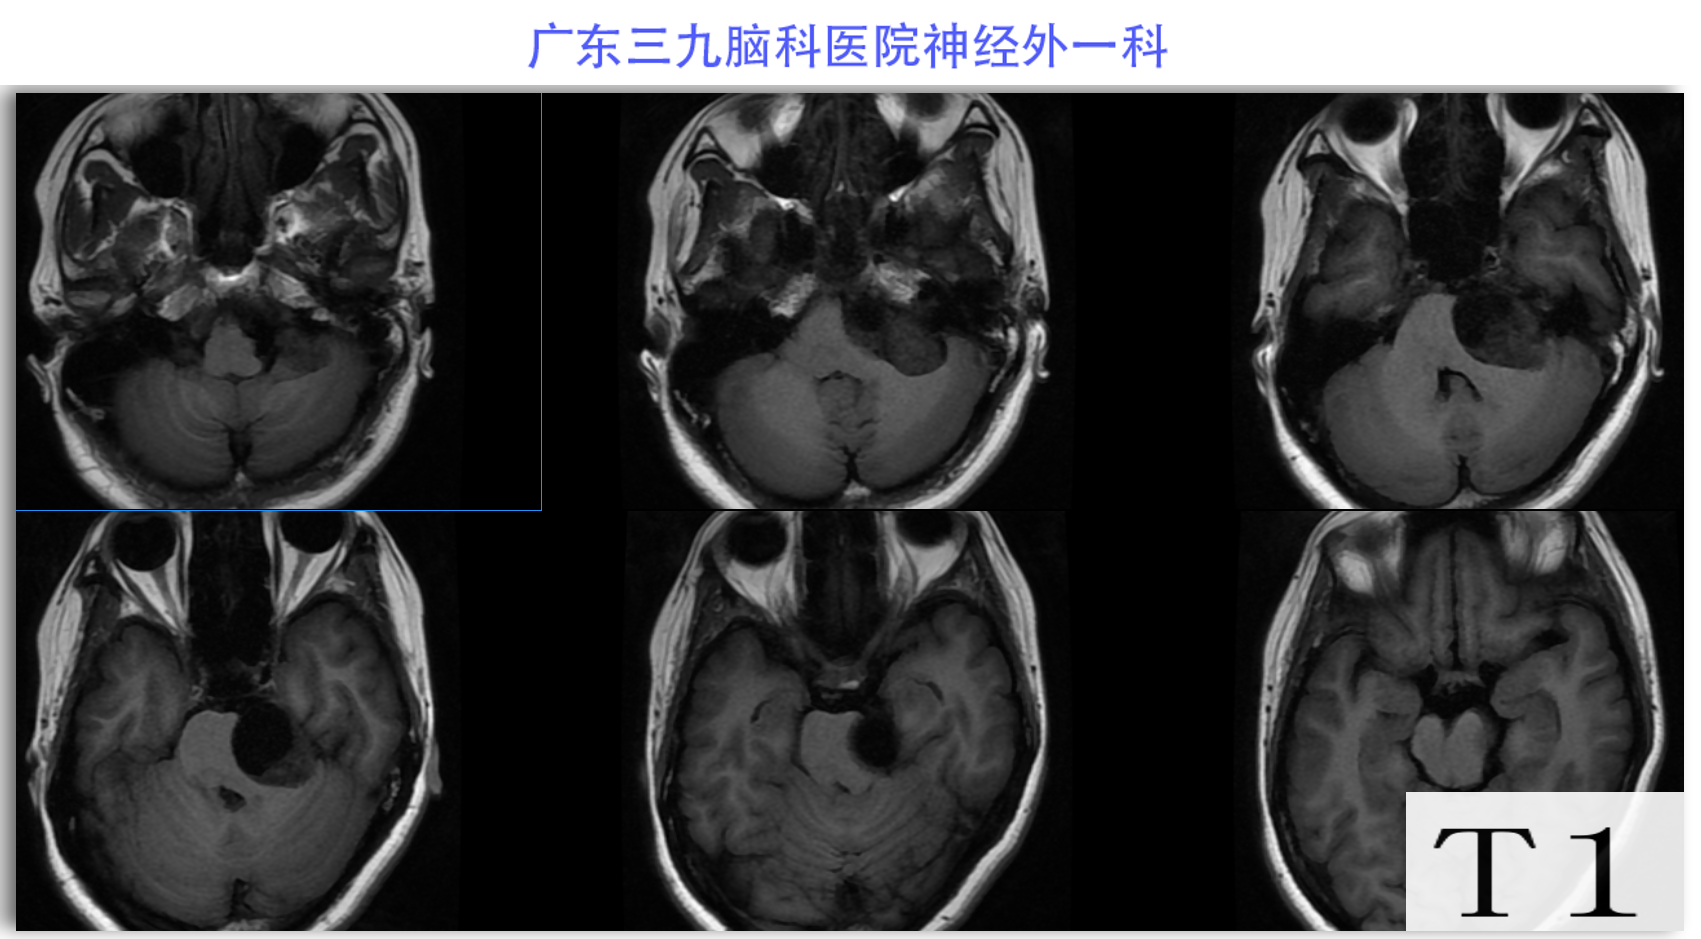

陈某某,女,41岁,因“左侧面部麻木3月余,吞咽困难半月余”于2024-02-17入院。患者3个月前出现左侧面部麻木,偶尔伴有头晕和左侧流泪,但没有听力下降或耳鸣。同时,患者也出现肢体乏力和行走不稳,但未接受任何治疗。半个月前,患者发现吞咽硬质食物稍有困难,同时左侧面部麻木加重。因此,前往当地医院就诊,并进行头颅MR检查,结果显示左侧CPA区存在占位性病变。为了进一步治疗,患者转诊至我院就医。术前检查显示:左侧角膜反射减弱,左侧鼻唇沟略微变浅,伸舌稍微右偏,咽反射迟钝。门诊诊断为“左侧巨大听神经瘤”,收治至我科进行住院治疗。手术过程顺利,术后患者恢复良好,面部轻度瘫痪与术前相同。术后病理检查结果确认为听神经瘤。